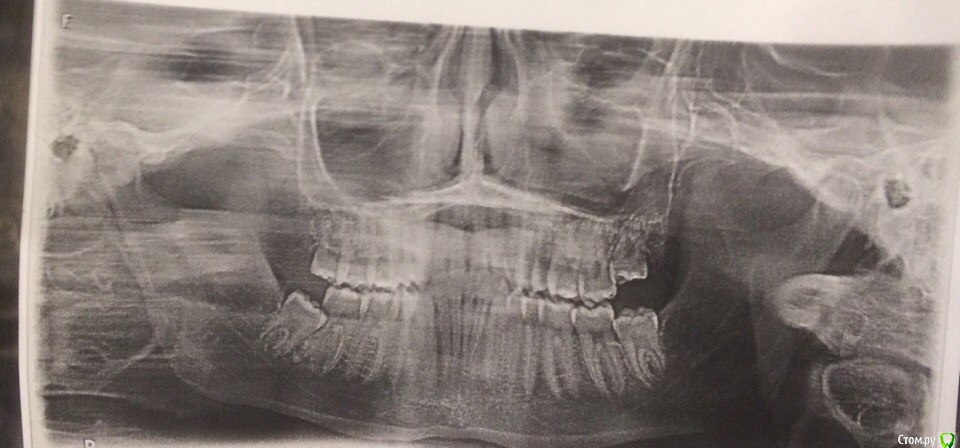

amiron Опубликовано 15 мая, 2017 Поделиться Опубликовано 15 мая, 2017 Подскажите, стоит ли удалять зуб мудрости снизу слева (см фото) ? Он не болит, только иногда зудит. И стоит ли удалять зуб мудрости справа снизу (см фото), он вообще не болит и не зудит. Ссылка на комментарий

St. Опубликовано 15 мая, 2017 Поделиться Опубликовано 15 мая, 2017 Стоит планово удалить и слева и справа, постольку им нет места в челюсти и если оставить как есть могут испортиться соседние зубы Ссылка на комментарий

red_butler Опубликовано 16 мая, 2017 Поделиться Опубликовано 16 мая, 2017 Все четыре удаляйте Ссылка на комментарий